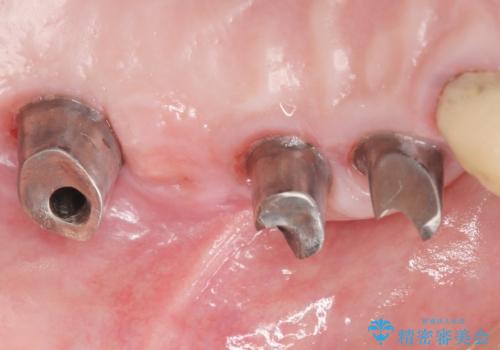

精査したところ、歯周病に罹患した歯を長年放置したことから骨吸収が進行し、上顎骨の厚みはとても薄くなっていました。

全顎的な歯周病治療を行ったのち、上顎洞底挙上術(上顎骨に骨を増やす手術)を併用したインプラント埋入を行いました。

インプラントの種類:ストローマン BLT